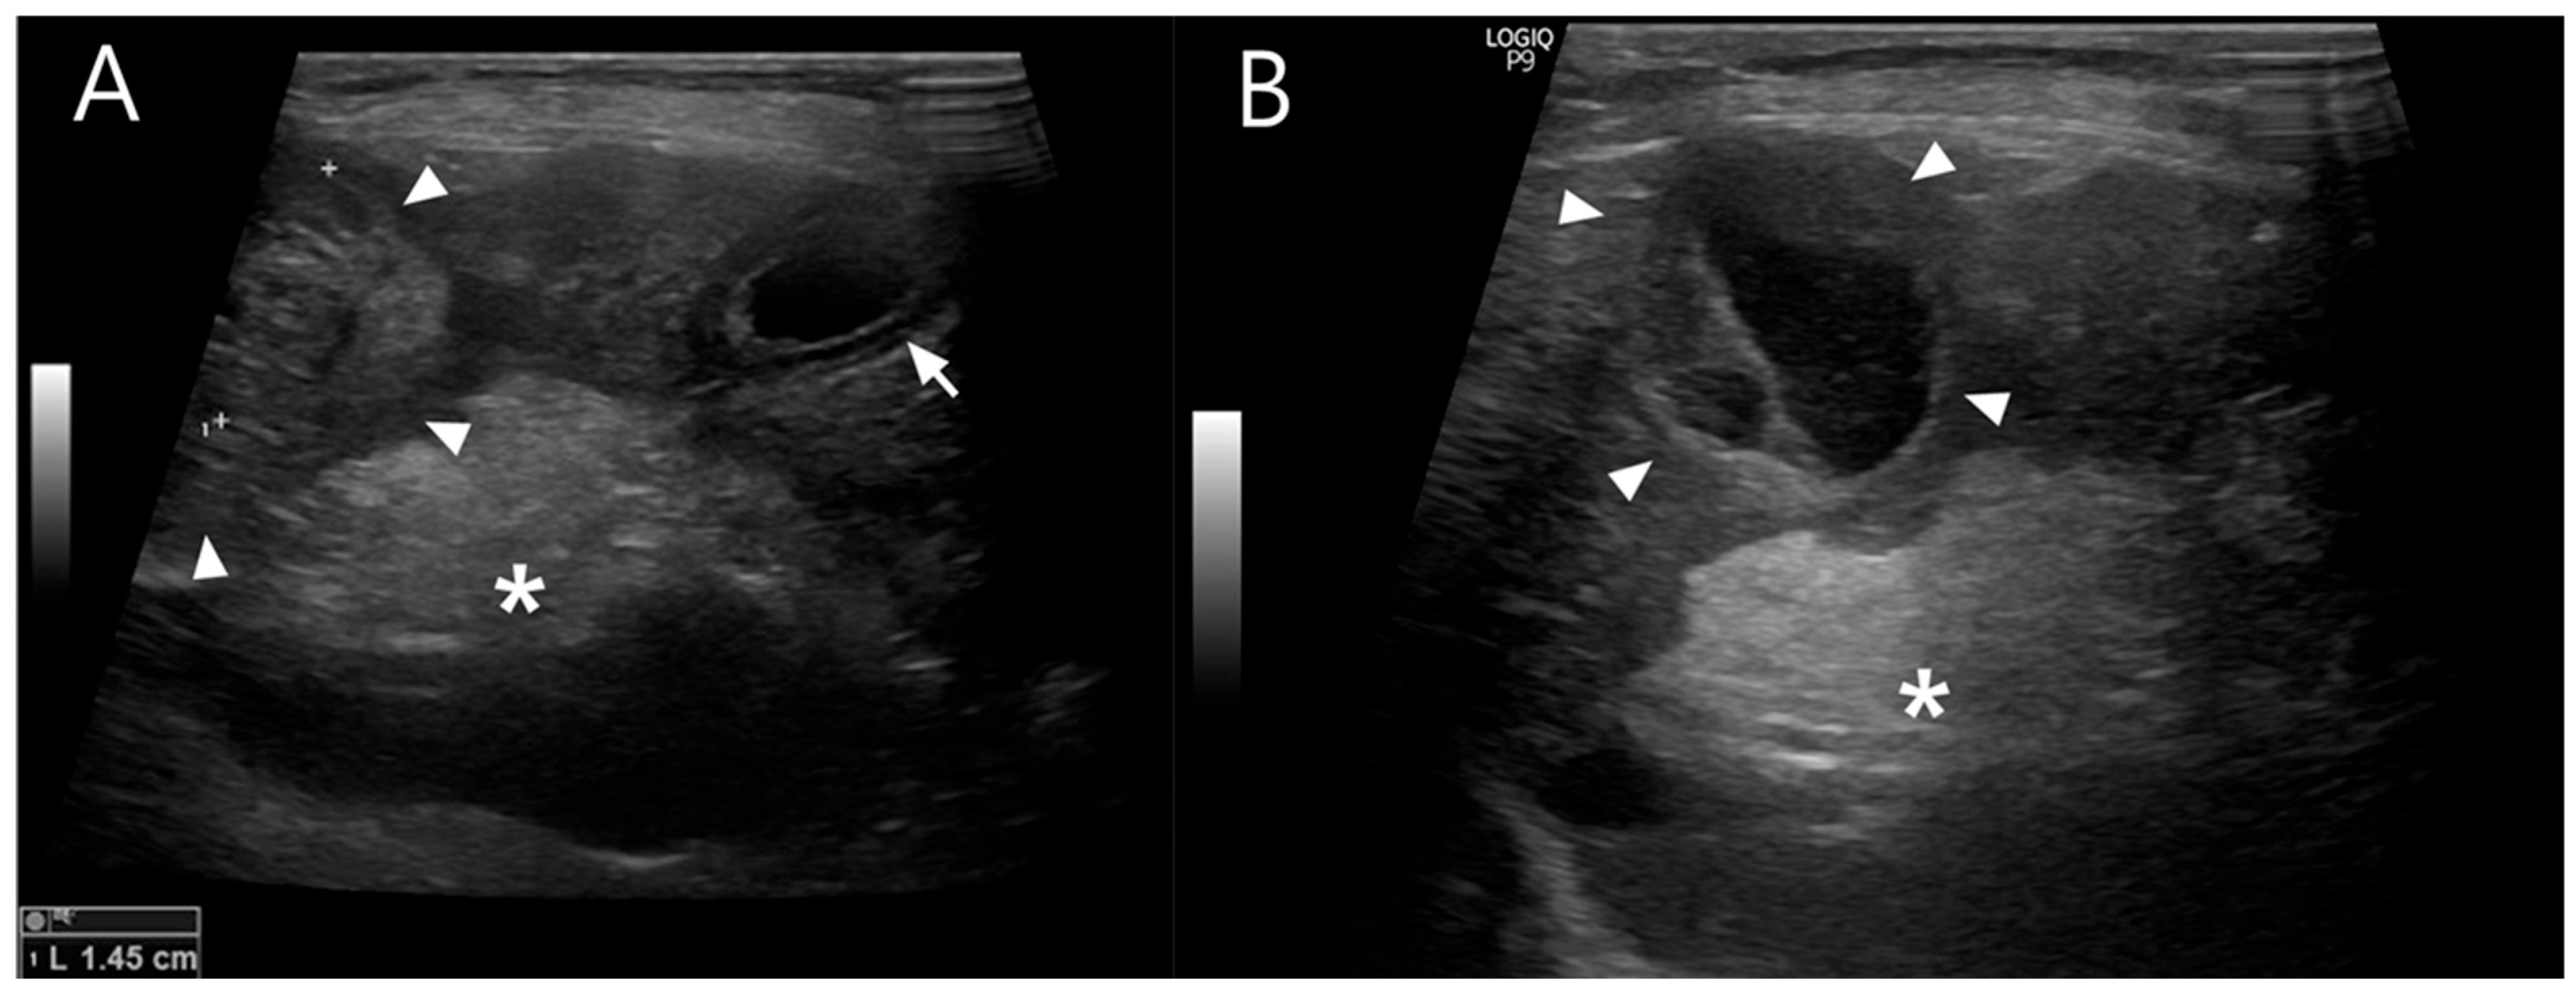

Abdominal ultrasonography showed progressive gallbladder wall thickening, localized hyperechoic peritonitis, and a heterogeneous hepatic nodule with internal anechoic, cyst-like structures (Figure 1), raising suspicion for hepatic abscess, cholangitis, or hepatitis. Concurrently, ultrasound-guided fine-needle aspiration (FNA) and bacterial culture with antibiotic susceptibility testing were performed. Grossly, the aspirated material was yellowish and slightly turbid, with a viscous, bile-tinged appearance consistent with a septic inflammatory process. Cytologic analysis of the FNA sample revealed numerous toxic neutrophils (Figure 2), and the hepatic nodule was diagnosed as a hepatic abscess.

Figure 1.

(A) Abdominal ultrasonographic image showing the liver and gallbladder. The gallbladder wall is thickened (arrow), displaying a double rim sign, which can be seen in cases of gallbladder edema, hypoalbuminemia, sepsis, or peritonitis. A region of increased echogenicity is present dorsal to the gallbladder (asterisk), suggestive of localized peritonitis. A heterogeneous hepatic nodule is also identified (arrowhead). (B) The hepatic nodule (arrowhead) appears round but atypical, containing internal septations and anechoic cyst-like structures. Increased echogenicity of the adjacent peritoneum beneath the nodule (asterisk) is noted, consistent with peritoneal reaction.